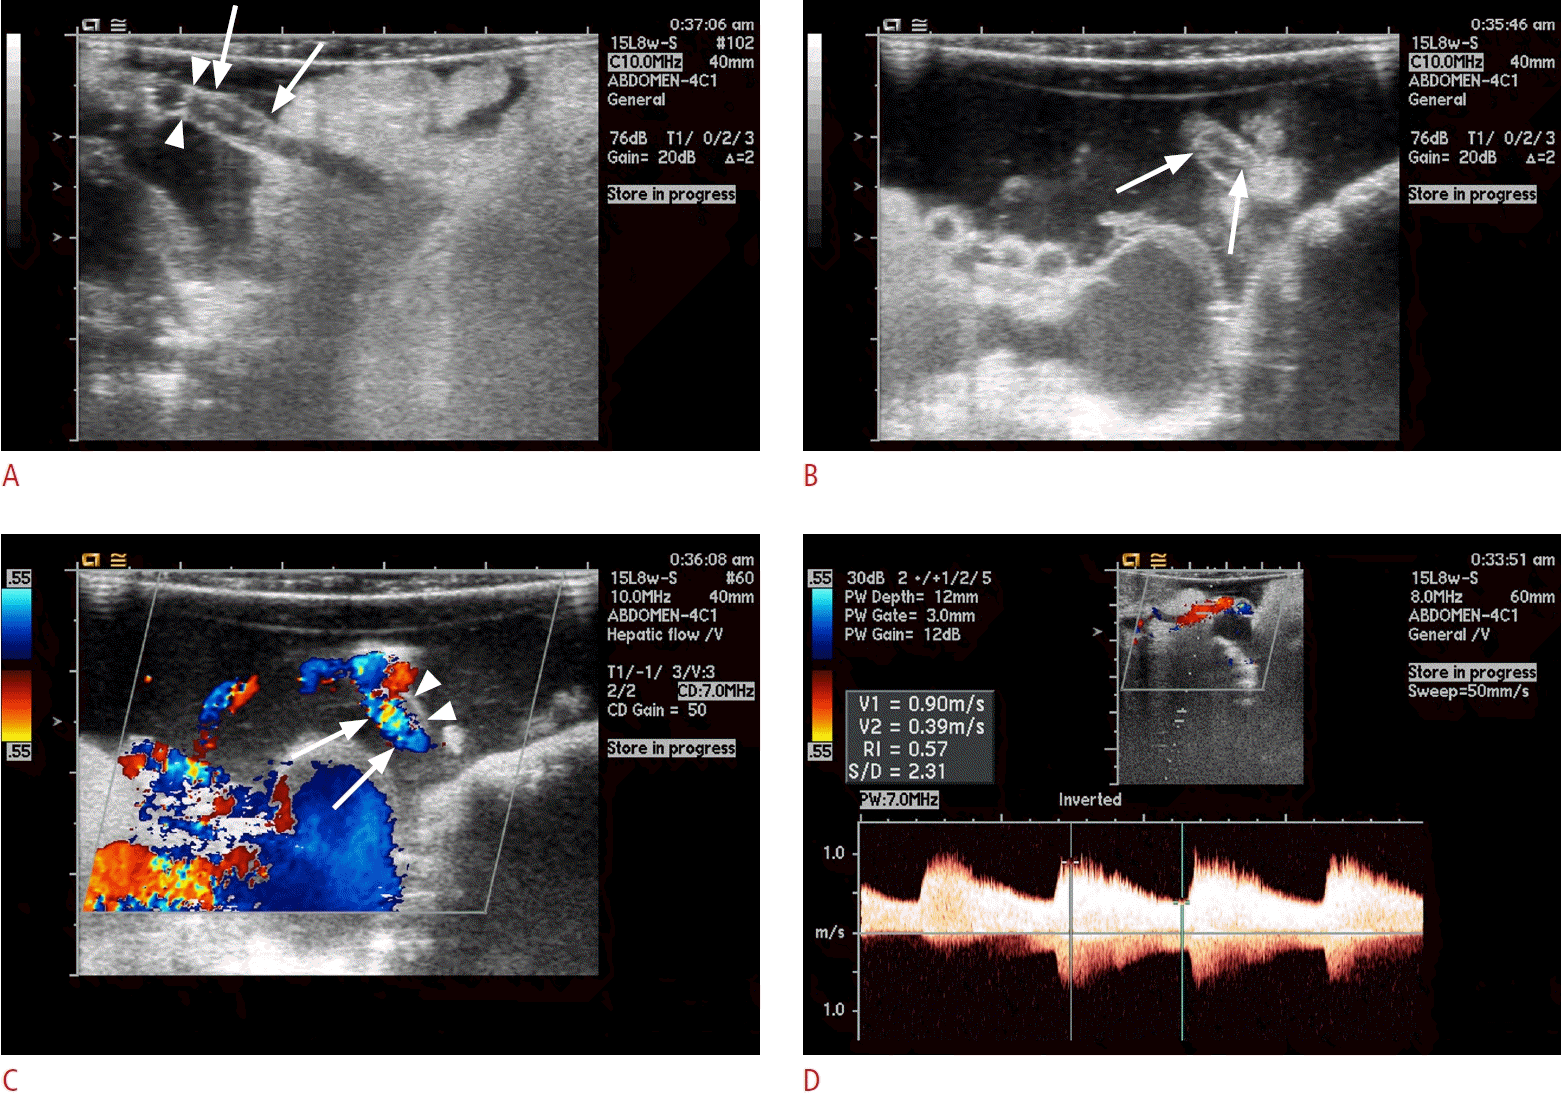

Fig. 2.

Hepatic artery stenosis on intraoperative ultrasonograms.

A. Grayscale intraoperative sonogram shows mild waisting and angulation around the anastomosis (dashed circle). B. Color Doppler ultrasonogram shows weak flow of the graft hepatic artery, marked as dark blue color (arrows). C. Spectral Doppler ultrasonogram shows tardus parvus waveform of graft hepatic artery, with decrease of resistive index (<0.5) and prolonged systolic acceleration time (>0.08 seconds). D. Following the revision of the anastomosis, spectral Doppler ultrasonogram shows restored normal waveform of graft hepatic artery.

Fig. 3.

Hepatic artery thrombosis on intraoperative ultrasonograms.

Intraoperative ultrasonograms in longitudinal (A) and tangential direction (B) show echogenic filling defect within the perianastomotic lumen which indicates a thrombus (arrows). Mild waisting in the anastomosis is also noted (arrowheads in A).

Fig. 4.

Hepatic artery dissection on intraoperative ultrasonograms.

A, B. Grayscale intraoperative sonograms show intimal flap (arrows) in the recipient hepatic artery lumen. Hepatic artery anastomosis is noted by short reverberation echoes from the stitches (arrowheads in A). C. Color Doppler ultrasonogram shows absence of color flow in the false lumen (arrowheads). Flow in the true lumen is not compromised (arrows). D. Doppler ultrasonogram shows spectral waveform of the graft hepatic artery within normal limit.